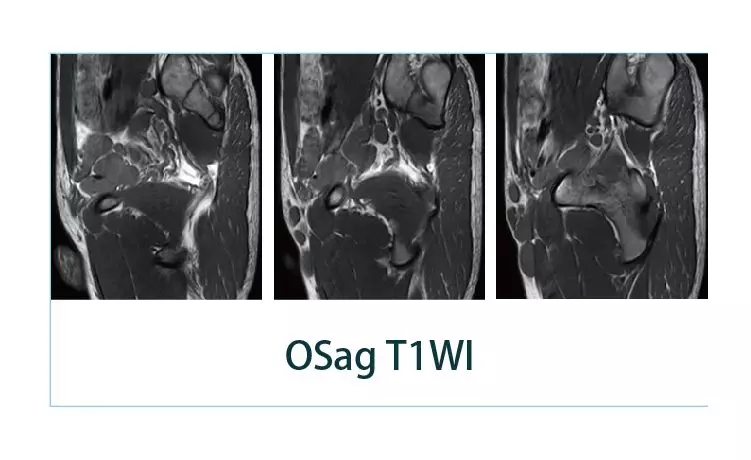

【朗润影像档案】20190405磁共振影像病例结果讨论

【朗润影像档案】磁共振影像病例分享(编号20190405)